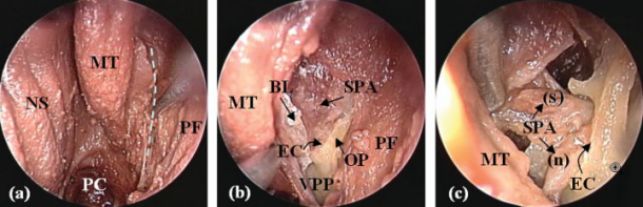

局麻下经股动脉穿刺右侧颈外动脉造影,可见蝶骨体底水平的黏膜有迟发性出血(箭头所示),考虑责任血管为上颌动脉的终末分支。

左图为一例新鲜尸头标本的左侧腭鞘管解剖。右图为该患者二次鼻内镜手术时所见(右侧),磨除腭骨蝶突后见出血来源于咽动脉,予以双极电凝烧灼并离断,同时可见初次手术时烧灼离断的蝶腭动脉。S 鼻中隔,SS 蝶窦,NPh 鼻咽,SPA 蝶腭动脉,PhA 咽动脉,sb-SPA 鼻中隔后动脉,nb-SPA 蝶腭动脉的鼻腔外侧壁分支,VC 翼管。